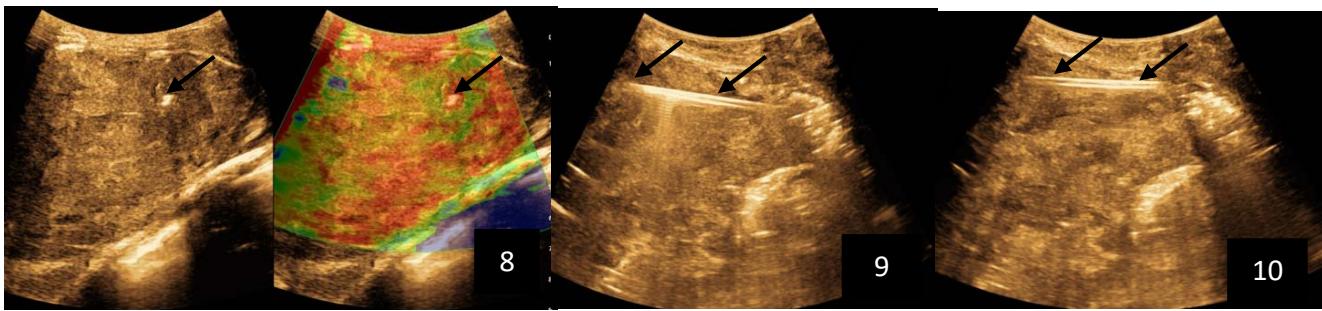

Tshibasu Tshienda et al. Percutaneous Radio-Guided Chemical Ablation with Absolute Ethanol of Cystic and Solid Lesions in Kinshasa Hospital Environments

Tshibasu Tshienda et al. Safety and Diagnostic Accuracy of Biopsy of Targeted Splenic Lesions Under Ultrasound Guidance Using the Multiple-Pass Technique Without Co-Axial in Kinshasa Hospitals